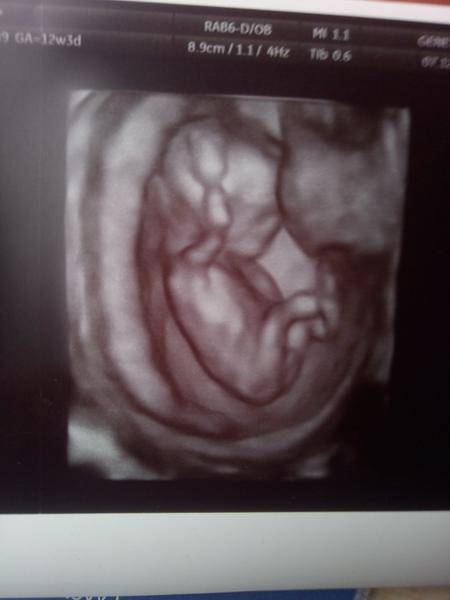

Pohlaví. Tipnete si? 🙂

Tohle je 50% kluk. Neni videt pohlavni hrbolek, neni podle ceho poznat.

@amazonkajanik Ne. Ve 13tt se urcuje pohlavi z profilu (sklon pohlavniho hrbolku vuci pateri), ale na tve prvni fotce videt neni. Z druheho typu fotky bude mozne urcovat az behem dalsich tydnu.

Podle me hrbolek videt jde a je to holcicka.

@katerina20 řekla bych, že holčička. Pohlavní hrbolek je rovnoběžně s páteří. Pak dejte vědět 😉 a hlavně hodně zdraví 🍀🍀🍀

Mne přijde, že z boku nic vidět být snad nemůže. I doktor, když mi to na 13+1 ukazoval, tak šteloval dítě aby bylo z profilu. Takže za mě 50 na 50 😀